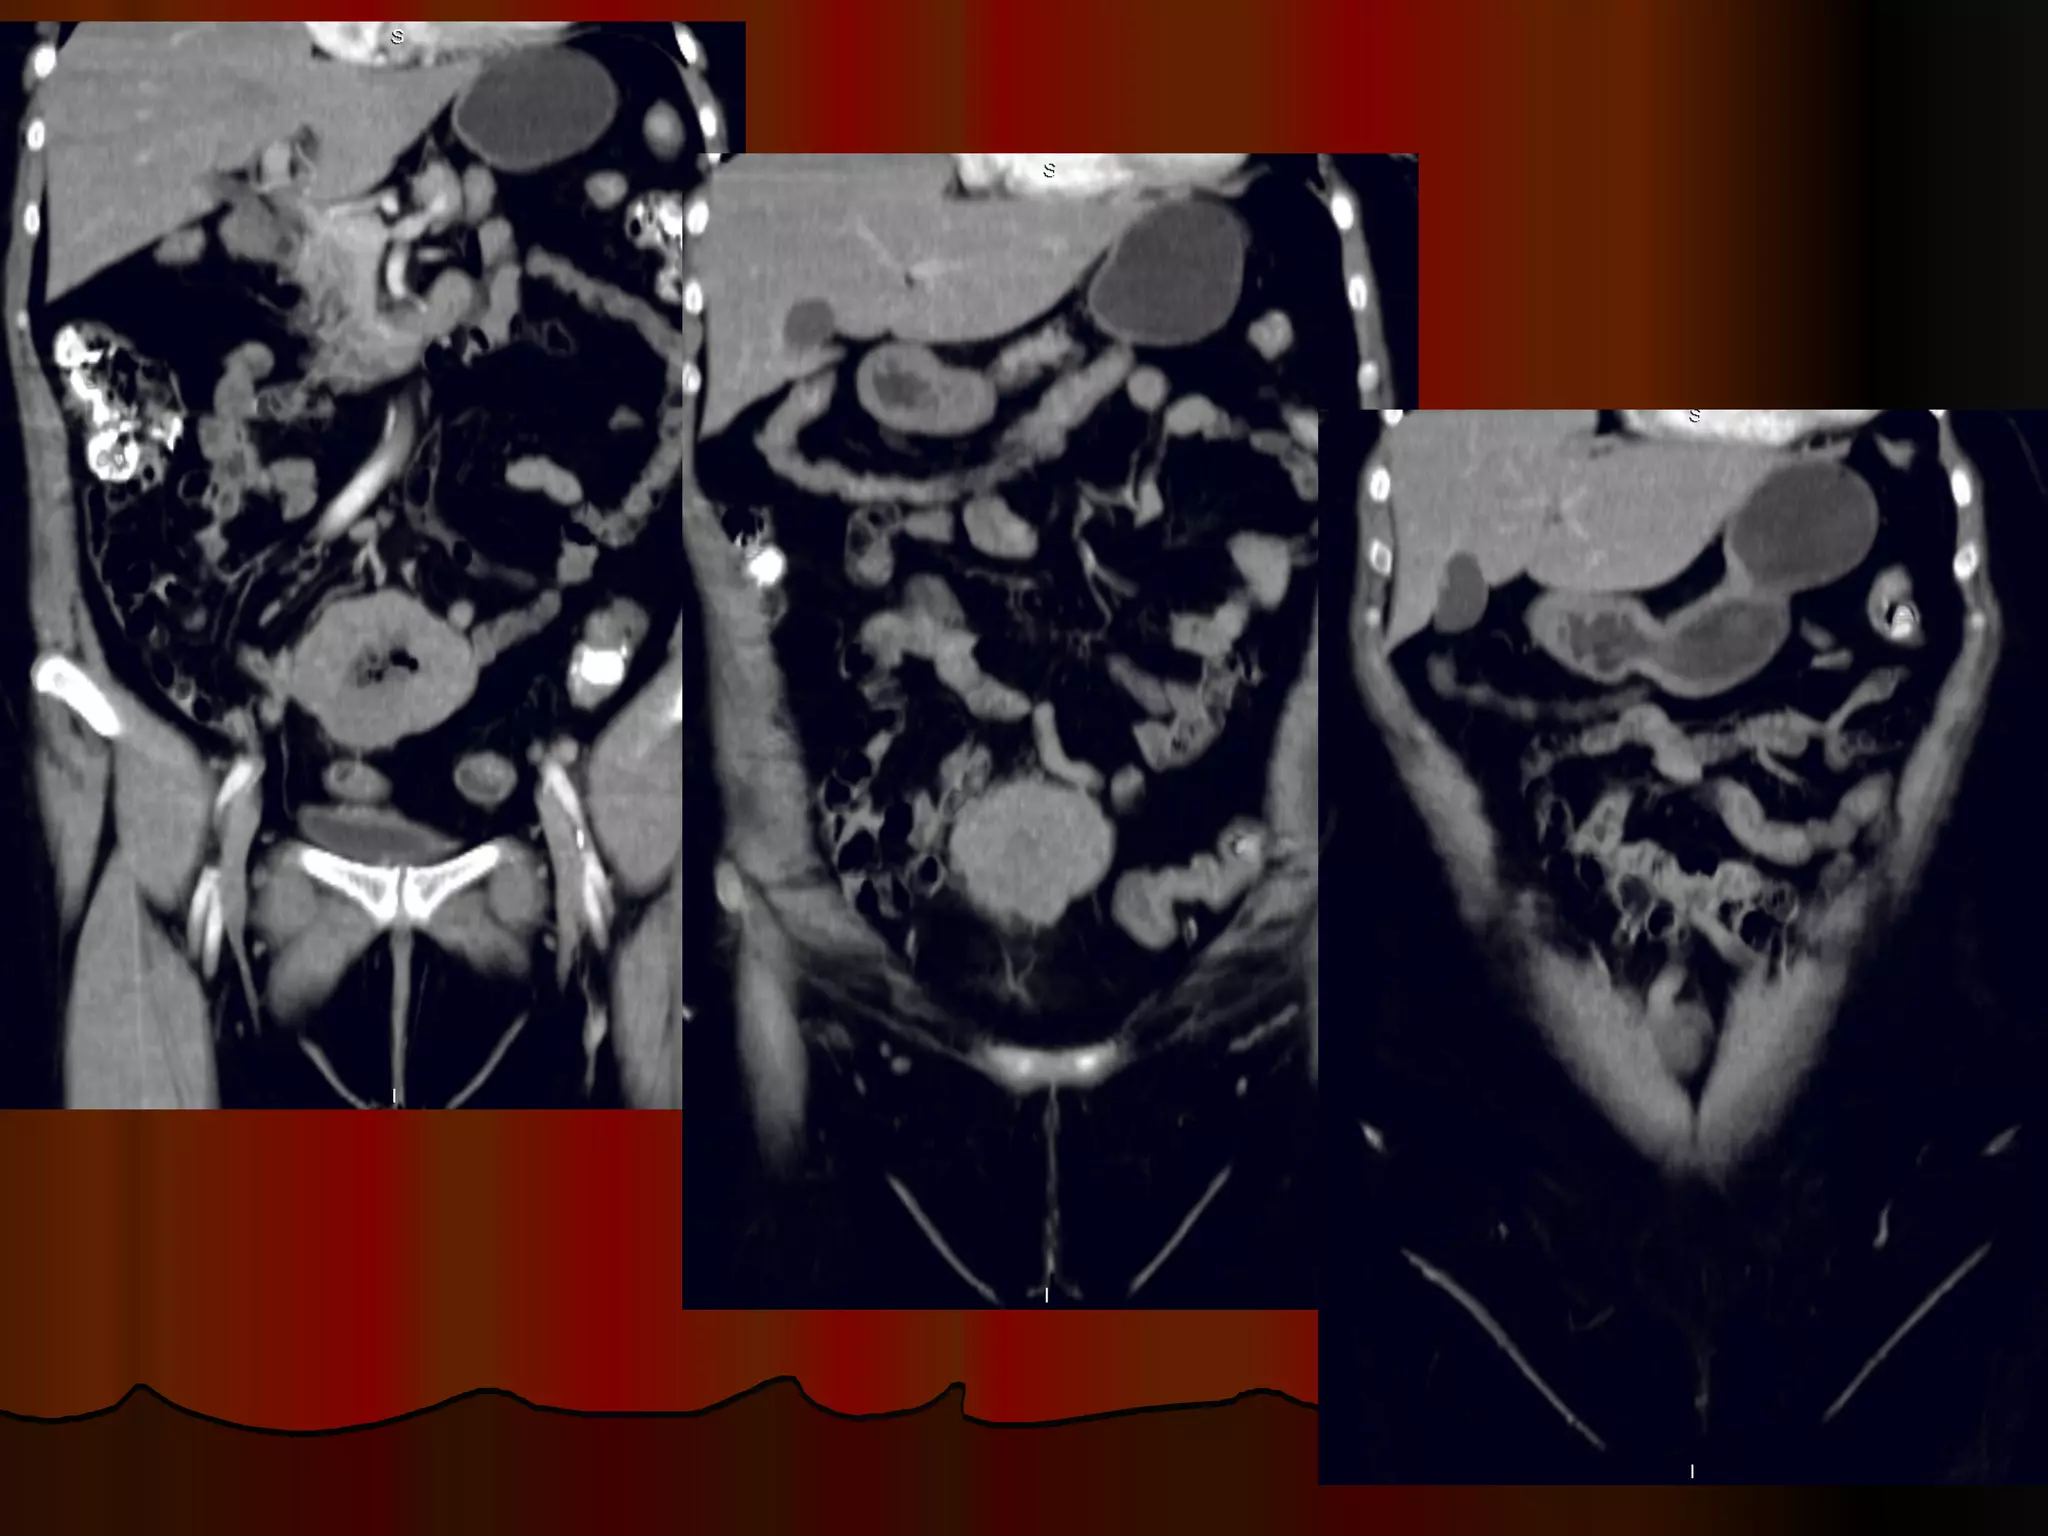

Женщина, 70 лет, боли в эпигастрии, анемия, резкая потеря веса Случай 4.

Инфильтративная форма рака желудка с региональным прорастанием, метастазы в яичники ( рак Крукенберга) и параректальную клетчатку ( Шницлеровский метастаз)

Женщина, 70 лет,боли в эпигастрии, анемия, резкая потеря веса Случай 4.

Инфильтративная форма ракажелудка с региональным прорастанием, метастазы в яичники ( рак Крукенберга) и параректальную клетчатку ( Шницлеровский метастаз)